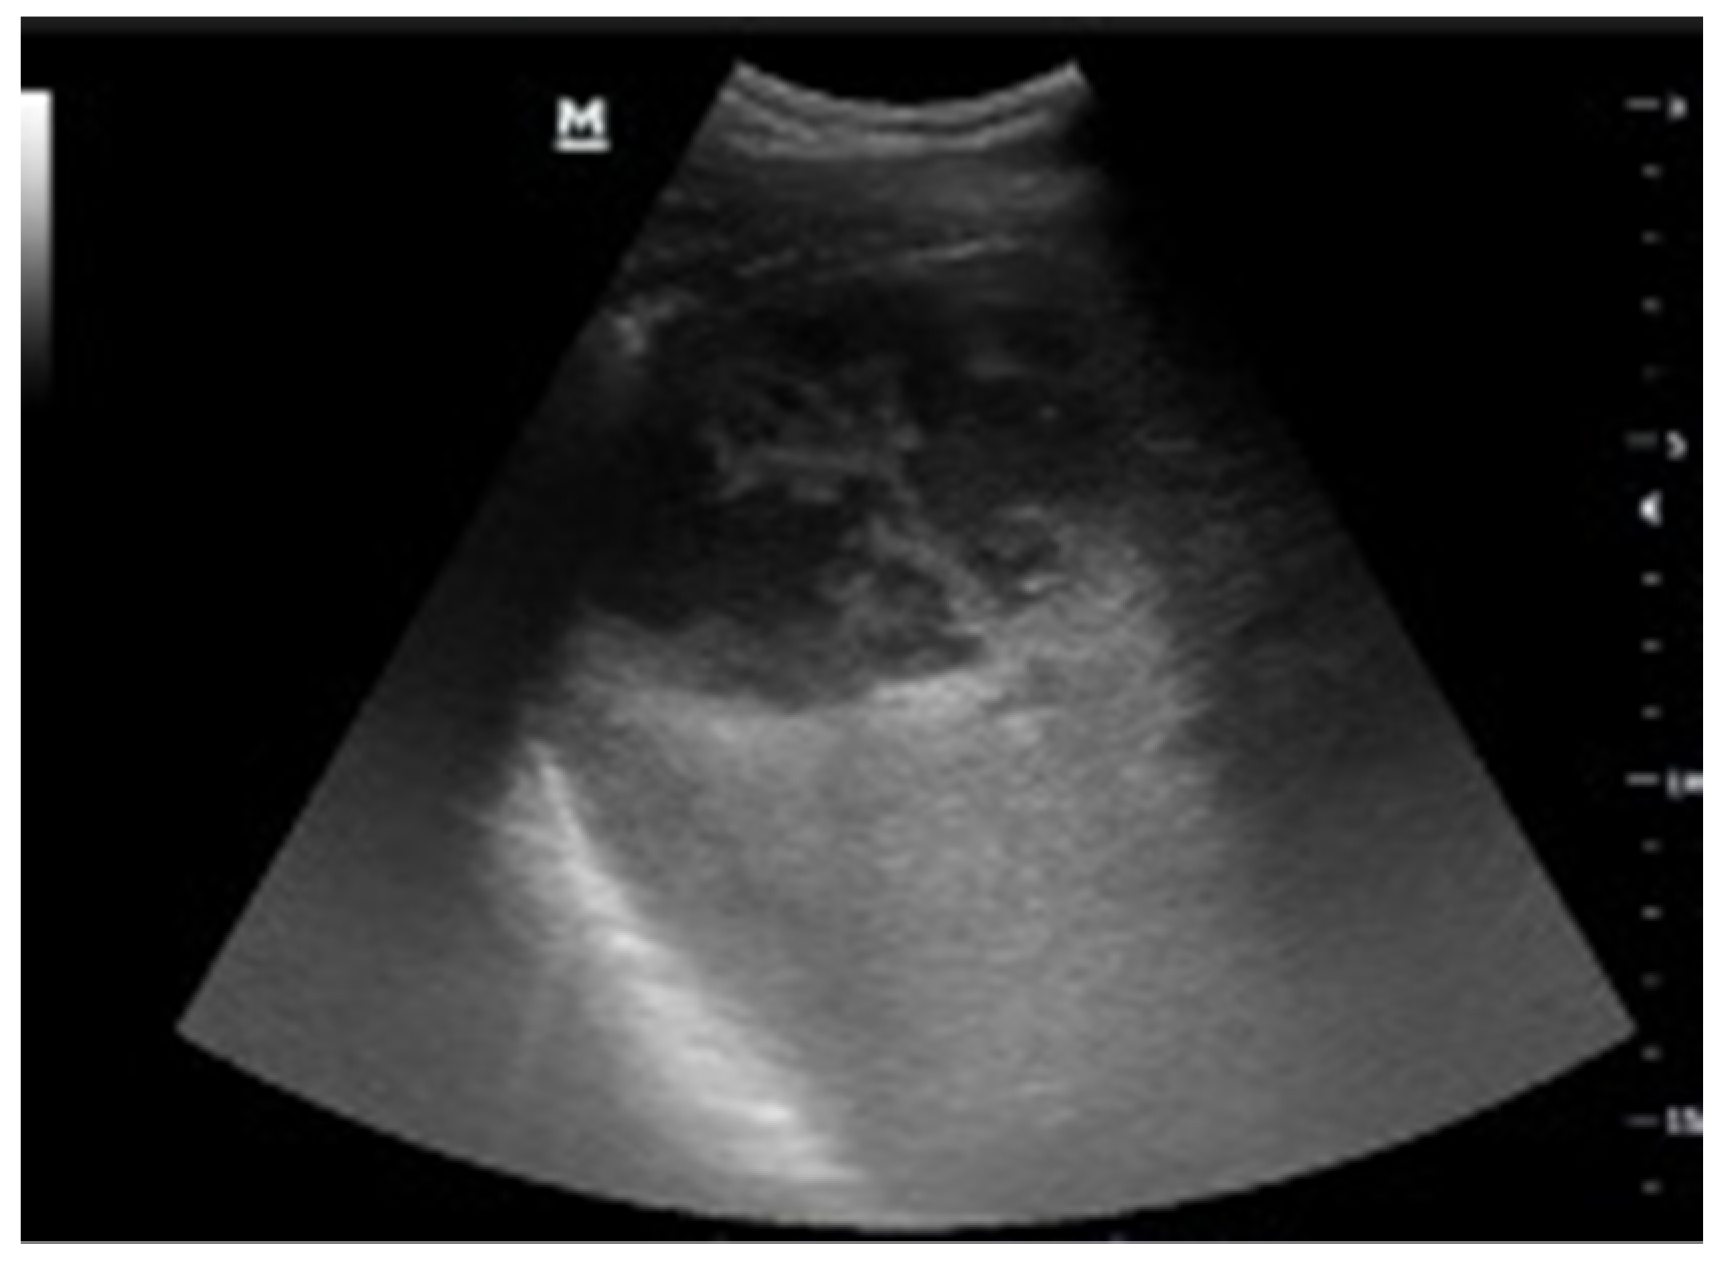

2.2.2. Urinary Tract

2.3.2. Urinary Tract

| Urinary Tract | Renal colic Urinary obstruction | Ruptured urinary tract Complicated renal colic Urinoma Extrarenal diffusion of inflammatory/infectious process | Lithiasis Pyonephrosis Blood, clot/hemorrhage Hemorrhagic cyst |

| Bladder | Overdistension | Perforation Perivisceral inflammation | Cystitis Endoluminal mass Blood clot Lithiasis |